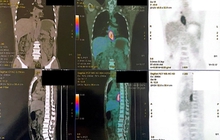

Hình ảnh PET/CT dày thành thực quản ⅓ dưới thâm nhiễm mỡ, chưa xâm lấn động mạch chủ ngực, tăng chuyển hoá FDG.

Trong quá trình thăm khám tai mũi họng, bác sĩ tiếp tục phát hiện khối u vùng hầu miệng. Mô bệnh học cho thấy đây cũng là ung thư biểu mô vảy sừng hóa xâm nhập. Chụp PET/CT ghi nhận tổn thương tăng chuyển hóa mạnh ở 1/3 dưới thực quản và vùng amydal trái, gốc lưỡi, kèm hạch cổ hai bên nghi ngờ di căn.